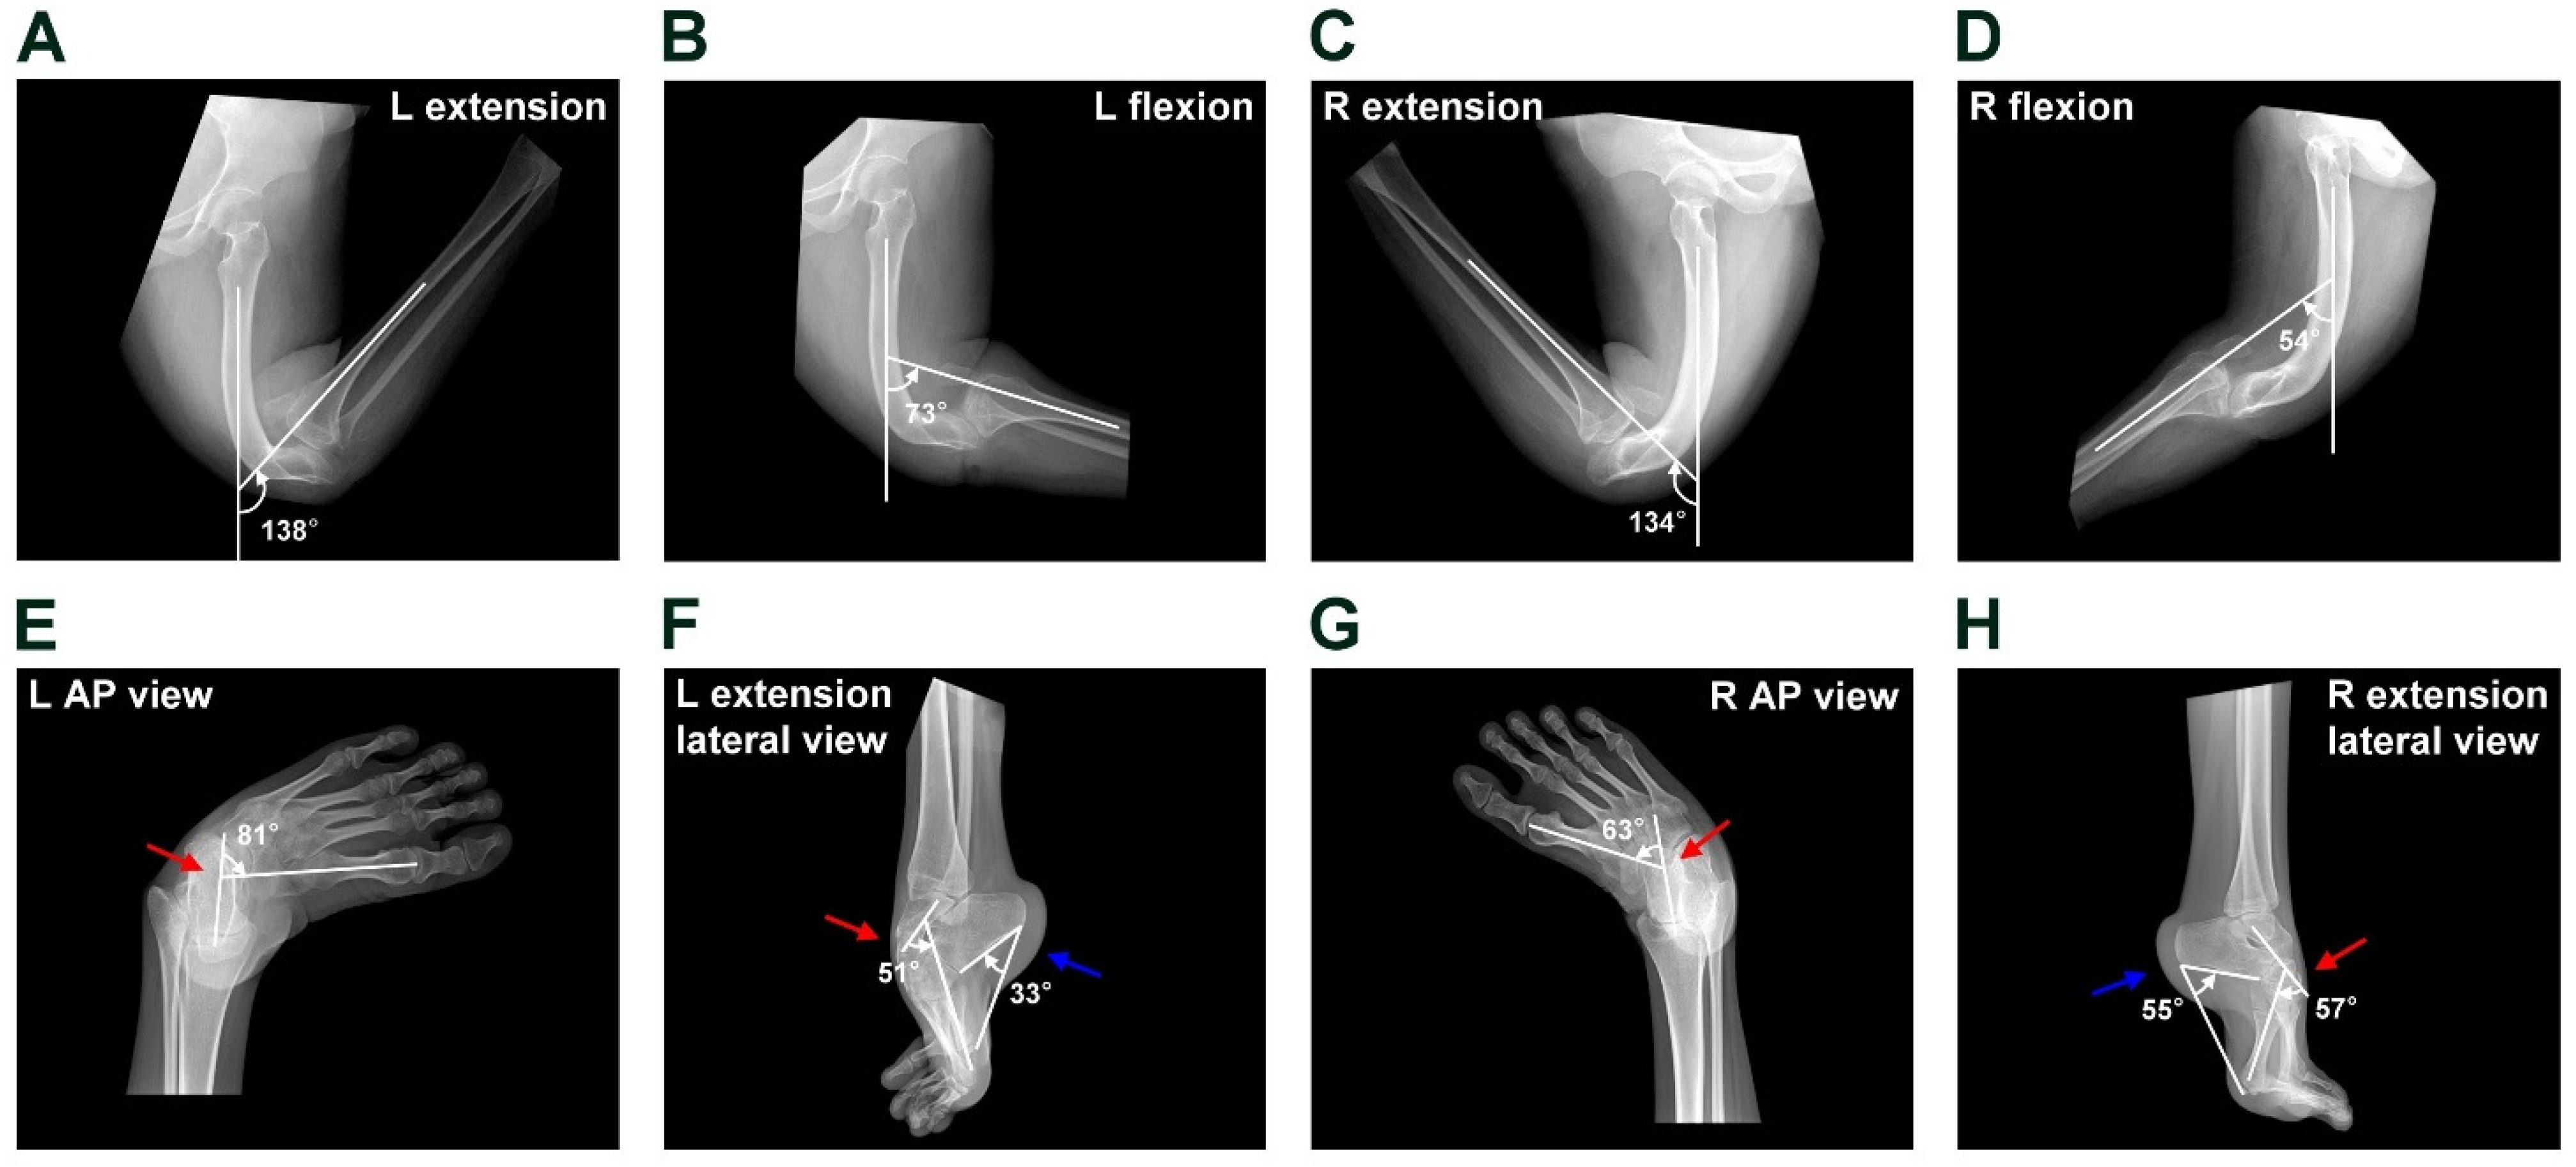

2.2. Physical Examination and Pre-Operative Image Findings

2.3. A Novel Surgical Technique for CGR

2.4. Complicated Surgical Procedure for Equinocavovarus Deformity and Ankle Flexion Contracture